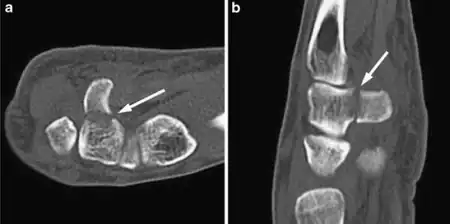

The cause is typically injury during racket sports, baseball, or golf or a fall onto the hand.[1][2] Types include hook (most common) and body (proximal pole, medial tuberosity, sagittal oblique, and dorsal coronal).[1] Diagnosis is typically by X-rays, but may require special views such as a carpal tunnel or supinated oblique view; or a CT scan.[1]

Diagnosis